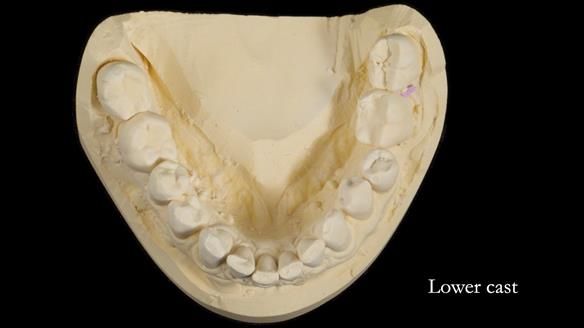

Welcome to Newsletter 64. I'll walk you through the process of providing a Mk 2 metal-based partial denture (RPD), for Ian a retired Veterinary Surgeon aged 78. The RPD was made at an increased vertical dimension and acted as an occlusal stabilisation splint - reducing the wear and bite force on the remaining natural teeth.